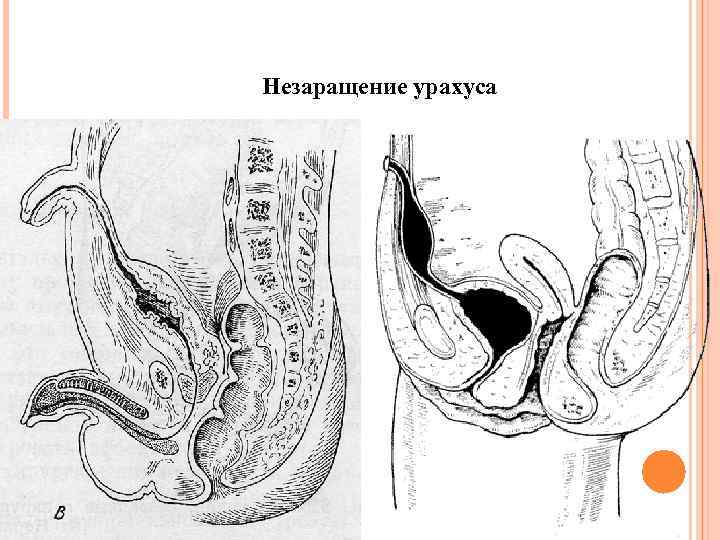

Незаращение урахуса

Незаращение урахуса